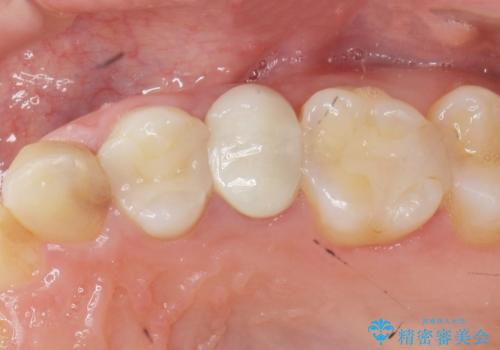

当初、歯ぐきよりも深い虫歯のぞんざいや、歯のポジションに問題がありましたがマルチブラケットを用いた部分矯正を行うことで適切な位置へと歯を移動させ、歯周環境を整えたセラミック治療を行うことができました。